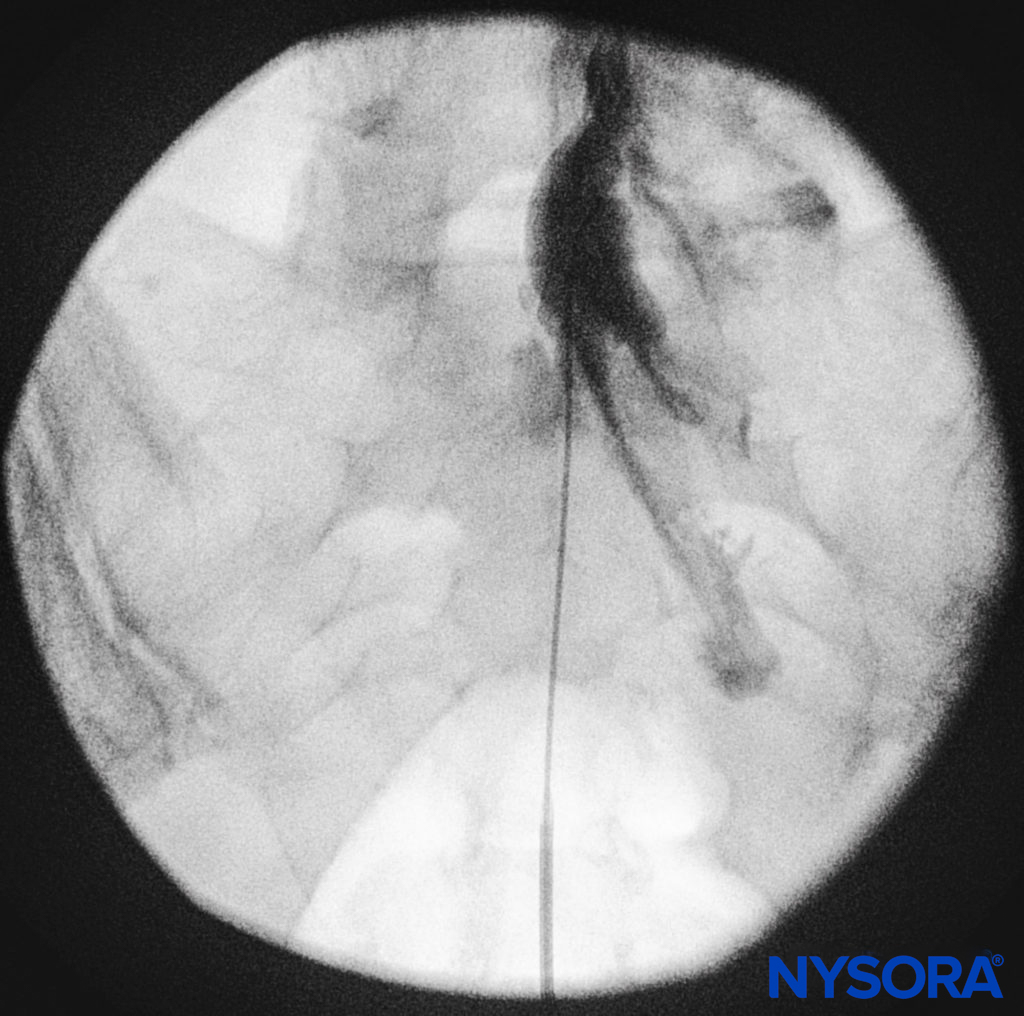

We utilize the anteroposterior view once the epidural needle is safely situated within the canal, and the epidural catheter is advanced cephalad (Figure 7, Figure 8). In this projection, the intermediate sacral crests appear as opaque vertical lines on either side of the midline. The sacral foramina are visualized as translucent and nearly circular areas lateral to the intermediate sacral crests. The presence of intestinal gas may obscure the recognition of these structures. A syringe loaded with either air or saline containing a small air bubble is then attached to the needle, and the loss-of-resistance technique is used to establish entry into the epidural space.

FIGURE 8. Anteroposterior fluoroscopic imaging depicting proper placement of the needle.

The catheters should be advanced gently because there have been reports of dural puncture with rapid or aggressive advancement. A lateral and anteroposterior fluoroscopic views should be obtained to demonstrate placement of the catheter in the epidural space (Figures 14 and 9) and to follow its path in a cephalad or cephalolateral direction. When the desired level is attained, iodinated nonionic contrast media may be injected, followed by the injection of local anesthetics, corticosteroids, or adjuncts (Figure 15). Usually, the catheter is not advanced higher than the level of L4 vertebral body, although it could be advanced to the L1 or L2 levels for specific indications. Some authors recommend not to advance the catheter more than 8–12 cm cephalad.

FIGURE 15. Anteroposterior fluoroscopic image depicting radiopaque contrast medium in the epidural space